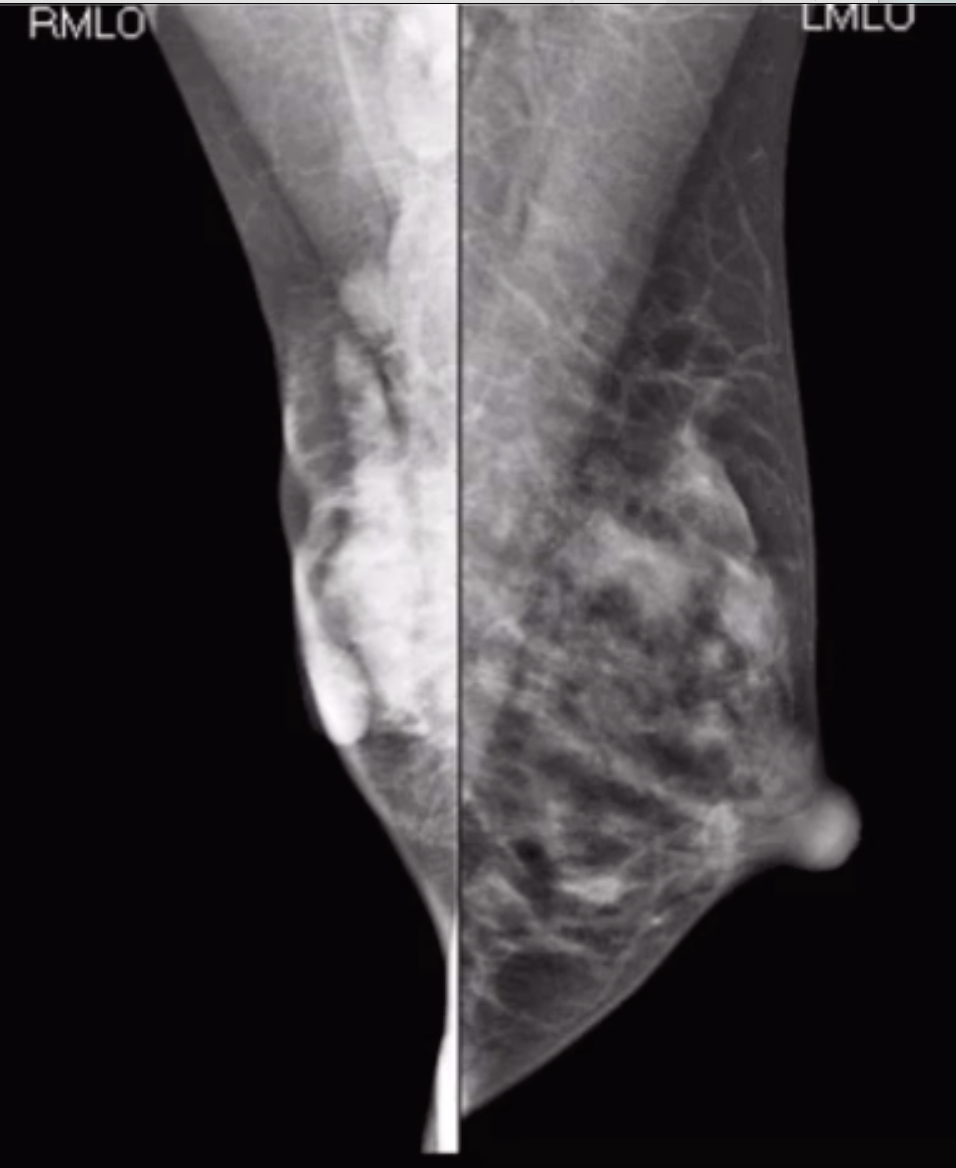

• Shrinking breast appearance on mammogram

• But may look normal on physical exam

• Breast wont compress because its infiltrated and fucked up

• Dark star appearance

• Architectural distortion without definitive central mass on MG

• Note skin thickening on left picture